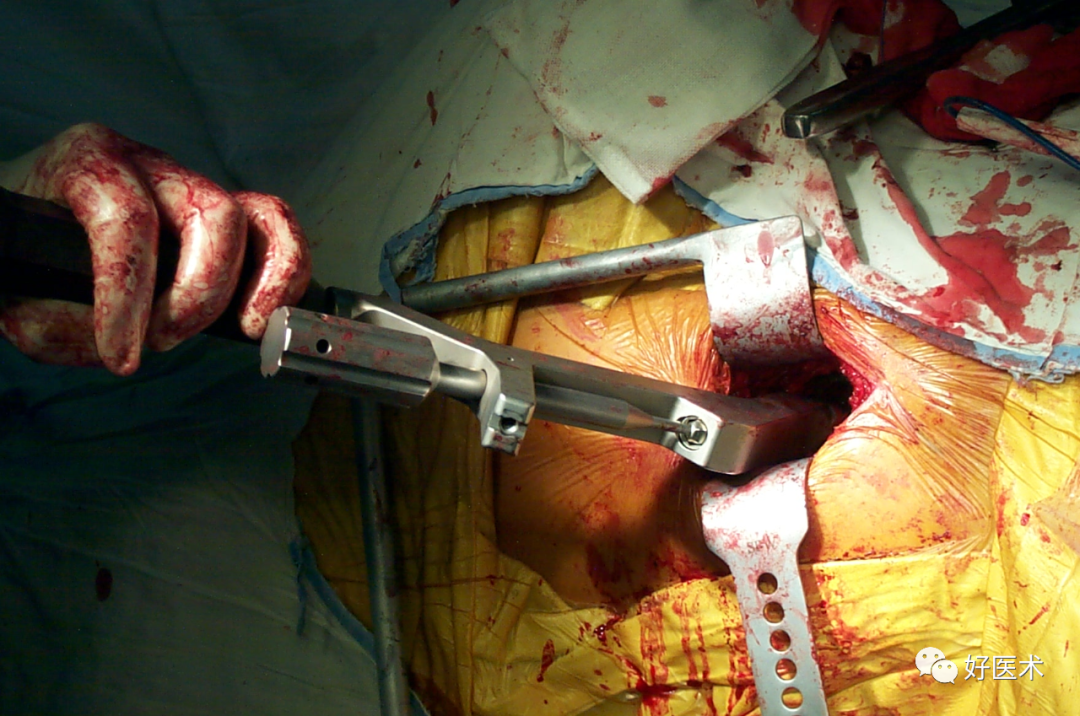

沿阔筋膜纤维方向切开扩筋膜大粗隆顶点臀中肌前1/3处沿纤维方向分离臀中肌

横形切开臀小肌2cm

沿大粗隆前缘切开臀中肌腱和臀小肌

切除关节囊髋关节内收、屈曲、外旋位脱位

准备髋臼

准备股骨髓腔

缝合切开之臀小肌和臀中肌